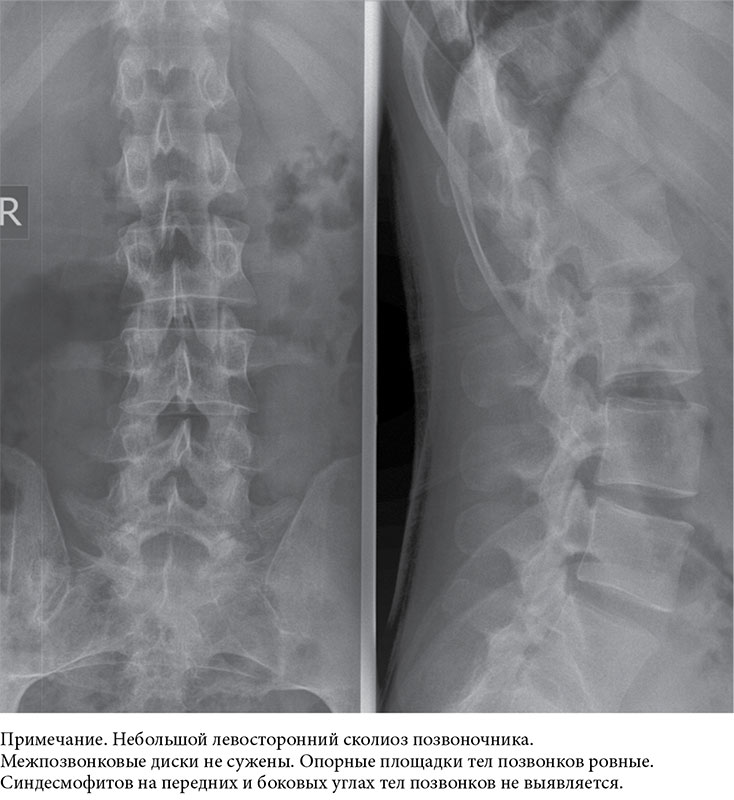

Рентген поясницы: анатомические особенности и медицинские исследования

Раздел: Фотоэссе